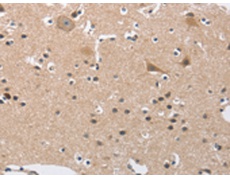

IHC positive control: |

Human brain and human thyroid cancer |

IHC Recommend dilution: |

50-200 |